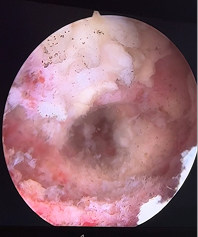

Рис. 5. Вид интраоперационной раны после удаления осколка. Виден свободный проходящий S1 корешок, участок частично резециорованного фасеточного сустава L5-S1, дефект после удаления осколка в центре раны.